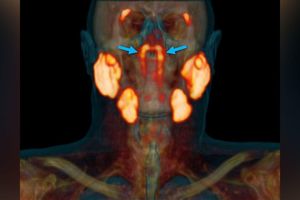

Một nhóm các bác sĩ chuyên khoa ung thư từ Hà Lan đã khám phá ra các tuyến nước bọt hoàn toàn mới ở 2 bên vòm họng của những bệnh nhân từng trải qua xạ trị ung thư, mà họ đặt tên là các tuyến hình ống. Nghiên cứu được công bố trên tạp chí Radiotherapy and Oncology hôm 1-1.

Theo đó, để tìm hiểu thêm về quá trình ung thư phát triển ở đầu và cổ, các bác sĩ đã sử dụng phương pháp quét bằng glucose phóng xạ để “làm nổi bật” một số khu vực trên cơ thể. Họ đã sử dụng phương pháp chụp cắt lớp phát xạ positron và chụp cắt lớp vi tính.Sau khi quét khoảng 100 bệnh nhân và thi thể, các bác sĩ vô cùng ngạc nhiên khi phát hiện một số khu vực trên khuôn mặt những bệnh nhân đã qua đời vẫn tiếp tục phát sáng.

Lúc đầu, họ cho rằng đó là một dạng bất thường nào đó, nhưng sau khi điều tra kỹ, nhóm bác sĩ nhận thấy họ đang xử lý một bộ phận hoàn toàn mới của cơ thể con người.

Cơ quan mới có kích thước tương đương với 3 tuyến nước bọt chính, là các tuyến ống tham gia sản xuất nước bọt trong miệng. Tuy nhiên, cơ quan mới này lại nằm ở hai bên vòm họng.

Phát hiện này phù hợp với mục tiêu chính của nhóm bác sĩ, đó là tìm hiểu thêm về bệnh ung thư. Theo đó, việc xạ trị tiêu diệt tế bào ung thư có thể đã gây ra các biến chứng với tuyến nước bọt, tạo nên những tuyến mới.

Trước đây người ta tin rằng các tuyến nước bọt hoặc chất nhầy trong vòm họng nhỏ hơn nhiều và trải đều khắp niêm mạc. Với phát hiện trên, các bác sĩ sẽ phải tránh nhắm mục tiêu vào phần mới này của cơ thể.